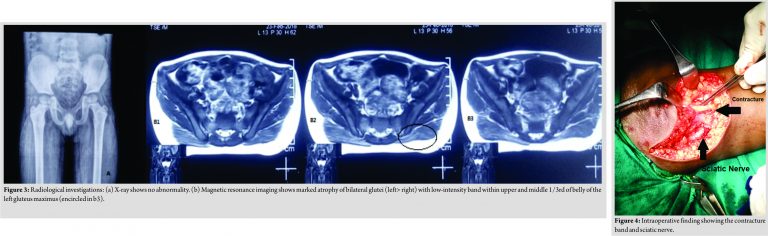

There was no significant pre-, peri-, or post-natal history. The child has no other significant history of previous illness apart from that febrile episode. He has no history of previous surgery or history of any long-term intake of medications. On examination, there was puckering in bilateral glutei muscle. There was atrophy and flattening of both glutei with left significantly more wasted than right (Fig. 2). Hip flexion was only 0–40° on both sides. Apart of flexion adduction and internal rotation was also restricted on both sides (Fig. 1b). There was no significant abnormality noted on plain radiograph (Fig. 3a). Magnetic resonance imaging (MRI) showed marked atrophy of bilateral glutei (left> right) with low-intensity band within upper and middle 1/3rd of belly of the left gluteus maximus. Mild medial retraction of distal body of the tendons of gluteus maximus was also noted (Fig. 3b).

After thorough evaluation, a diagnosis of bilateral gluteus maximus muscle contracture was made and he was planned for open release of contracture. Open release of contracture was done in two separate settings at an interval of 1 week. The left side was operated before the right side. On the left side, we released the gluteal muscle from the iliac crest, but it did not improve the range of motion of hip joint, then we cut the gluteus maximus tendon and fibrotic band near greater trochanter, after cutting the tendon, we were able to flex the hip joint to >90°. On the right side, we did not attempt to release gluteus muscle from the iliac crest as we found it to be ineffective. Only the tendon and fibrotic band were released following which an improvement in flexion noted intraoperatively. Sciatic nerve was identified and protected in both procedures (Fig. 4). Post-operative period was uneventful and there was no complication related to wound healing. Gradual passive physiotherapy and range of motion exercise were started 2–3 days after surgery. After 1 year of follow-up, the child had good range of motion. He was able to squat and sit cross-legged. Hip extension was possible in both hips. There was hypertrophic scar formation on both sides, for which he was advised treatment, but the parents refused for treatment (Fig. 5) (Video 2).